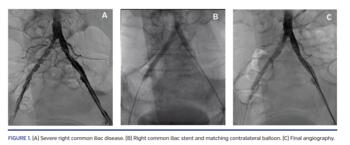

Received wisdom for aortoiliac bifurcation stenting typically dictates the kissing-stent approach using two stents even if critical disease is limited to one side in order not to compromise the contralateral common iliac ostium (CIO). We hypothesized that when critical disease is limited to just one CIO and the contralateral CIO is relatively disease free, one can get away with a single balloon-expandable stent straddling the diseased CIO if the contralateral CIO is protected with a simultaneous matching balloon inflation.

Five patients with a mean age of 65 years were identified; 60% were males, diabetic, and smokers. All patients had disabling unilateral hip and thigh claudication. They underwent stenting of diseased CIO with bare-metal stent while the contralateral CIO was protected with matching balloon inflation. Mean stent diameter and length were 7.8 mm and 46 mm, respectively. Mean matching balloon diameter and length were 7.4 mm and 32 mm, respectively. All target and contralateral CIOs were approached from the ipsilateral common femoral artery (CFA) except one non-diseased CIO, which was approached from the left axillary artery due to severe CFA disease. There were no procedural complications. Non-target CIO remained uncompromised in all cases. All patients went home the next morning and were symptom free at 1 month.

Contrary to received wisdom, predominantly unilateral aortoiliac bifurcation disease can be safely treated with a single stent if the contralateral CIO is protected with matching balloon inflation. Larger studies on this novel approach with a longer clinical follow-up are needed to validate our results.